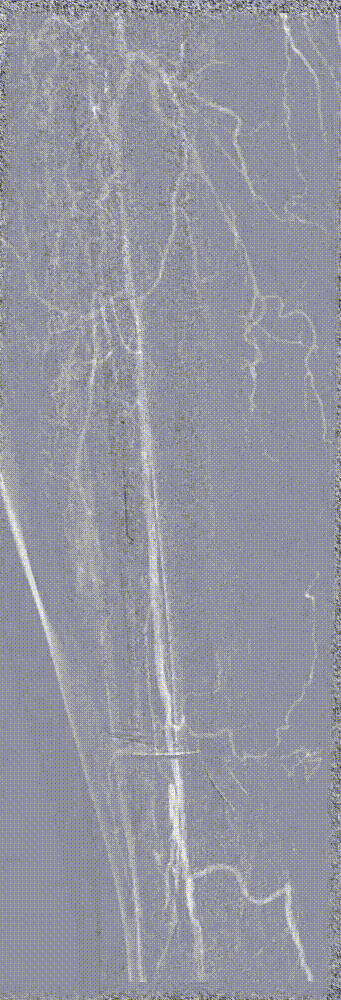

步进造影配合血管腔内超声诊断导管提示:股浅动脉全程、腘动脉、胫腓干动脉血流通畅,未见明显夹层、造影剂外溢,远端未见栓塞,膝下动脉如前。

腘动脉压力:90mmHg,比值0.73(原比值 0.54)

足背动脉压力85mmHg,比值0.69(原比值 0.45)

腘动脉压力:120mmHg,比值0.98 (原比值 0.65)

胫后动脉压力:118mmHg,比值0.96(原比值 0.54)

足背动脉压力:115mmHg,比值0.93(原比值 0.59)